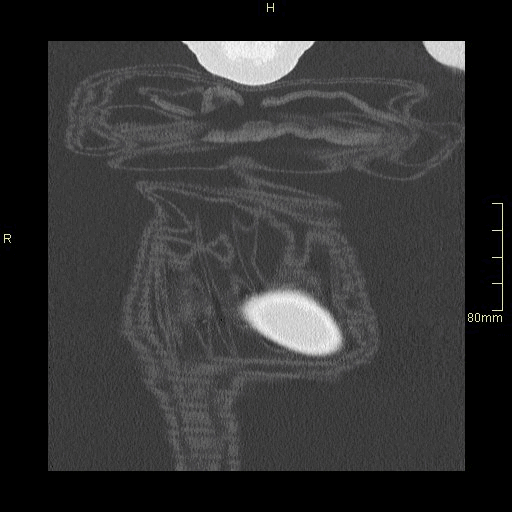

HRCT - Axial Prone Inspiration (Lung Window)

HRCT - Axial Supine Inspiration (Lung Window)

HRCT - Axial Supine Expiration (Lung Window)